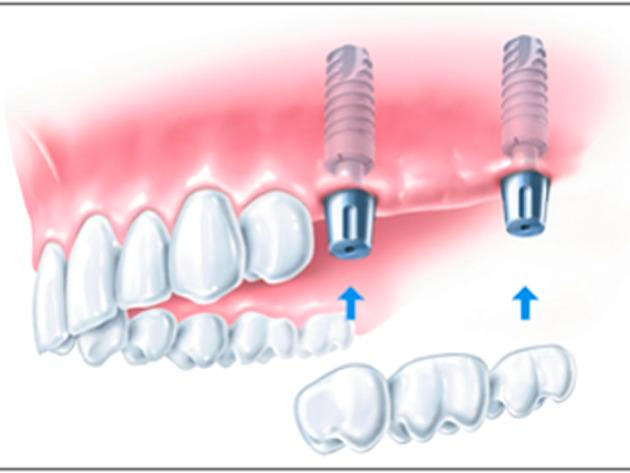

Einzelzahnlücke

Der Verlust eines einzelnen Zahnes kann jeden treffen. Oft sogar innerhalb von Sekunden: Sport gemacht, Zahn weg. Das ist zwar erschreckend, aber heute kein Drama mehr.

Implantate lösen das Problem naturnah und "unsichtbar". Zahnimplantate sind kleine, hoch entwickelte und ausgesprochen leistungsfähige Titanschrauben, die anstelle natürlicher Zahnwurzeln in den Kiefer gesetzt werden und fest in den Knochen einwachsen. Eine provisorische Versorgung kaschiert die Lücke, bis das Implantat eingeheilt ist.

Anschließend wird darauf "unsichtbar" und dauerhaft stabil Ihre neue Zahnkrone befestigt. Sie sitzt mit ihrer neuen Wurzel fest im Kiefer und ist von den natürlichen Nachbarzähnen nicht zu unterscheiden.